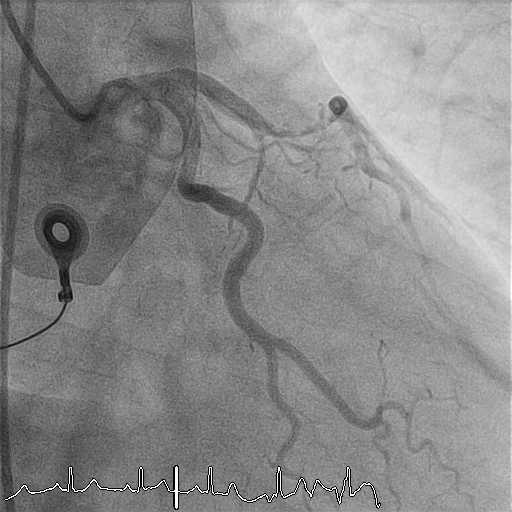

Pre-dilatation was performed with an IKAZUCHI ZERO 2.5 ¡¿ 15 mm balloon at 9–12 atm. Given the massive thrombus burden and prior incomplete systemic streptokinase infusion, intracoronary streptokinase was administered via the aspiration catheter in 1-mL aliquots (15,000 IU each), slowly over 1–2 minutes per dose, to a total of 150,000 IU. Progressive improvement in thrombus dissolution was observed with restoration of distal flow.Following thrombus resolution, direct stenting of the proximal LAD was performed using a Xience PRO-A 3.0 ¡¿ 23 mm drug-eluting stent, deployed at 9 atm. Post-dilatation was performed with a CONQUEROR NC 3.0 ¡¿ 15 mm balloon at 12–20 atm achieving full stent expansion. Final angiography demonstrated TIMI 3 flow with no dissection or residual stenosis.Given reduced LV systolic function, an IABP was inserted via the right femoral artery for hemodynamic support. Total contrast volume was 120 mL, total fluoroscopy time 10.03